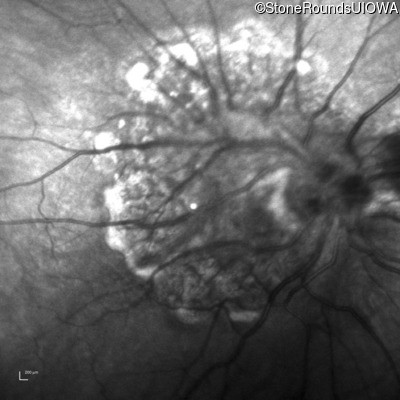

Infrared Fundus Photograph - Right - 20/2000

Exemplar